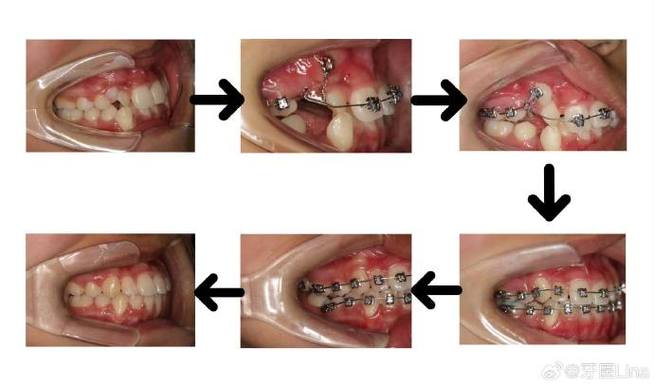

(图片来源网络,侵删)

(图片来源网络,侵删)- 最常用位置之一。 尖牙牙根粗壮,位置相对靠前,容易操作,是很多牵引的起点或终点。

- 适用牵引: 颌内牵引(如尖牙远中移动)、颌间牵引(如II类牵引需要上颌尖牙钩)、颌外牵引(如口外弓)。

- 放置方式: 尖牙托槽本身可能带有牵引钩(如拉钩托槽),或者需要在托槽上额外焊接一个牵引钩(尤其当需要更强力量或特定方向时)。